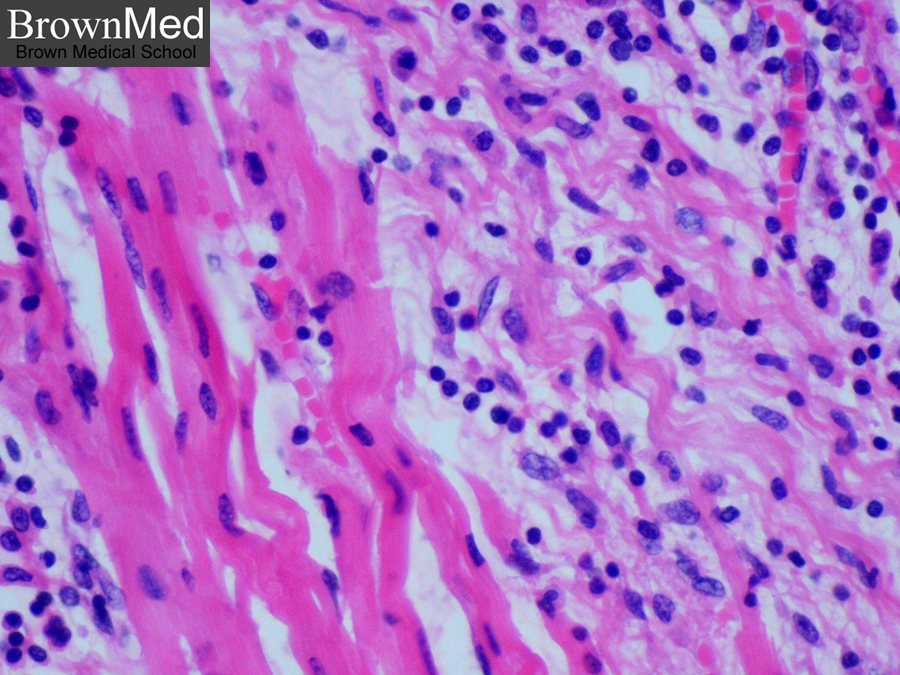

Межуточный миокардит: гистологические исследования